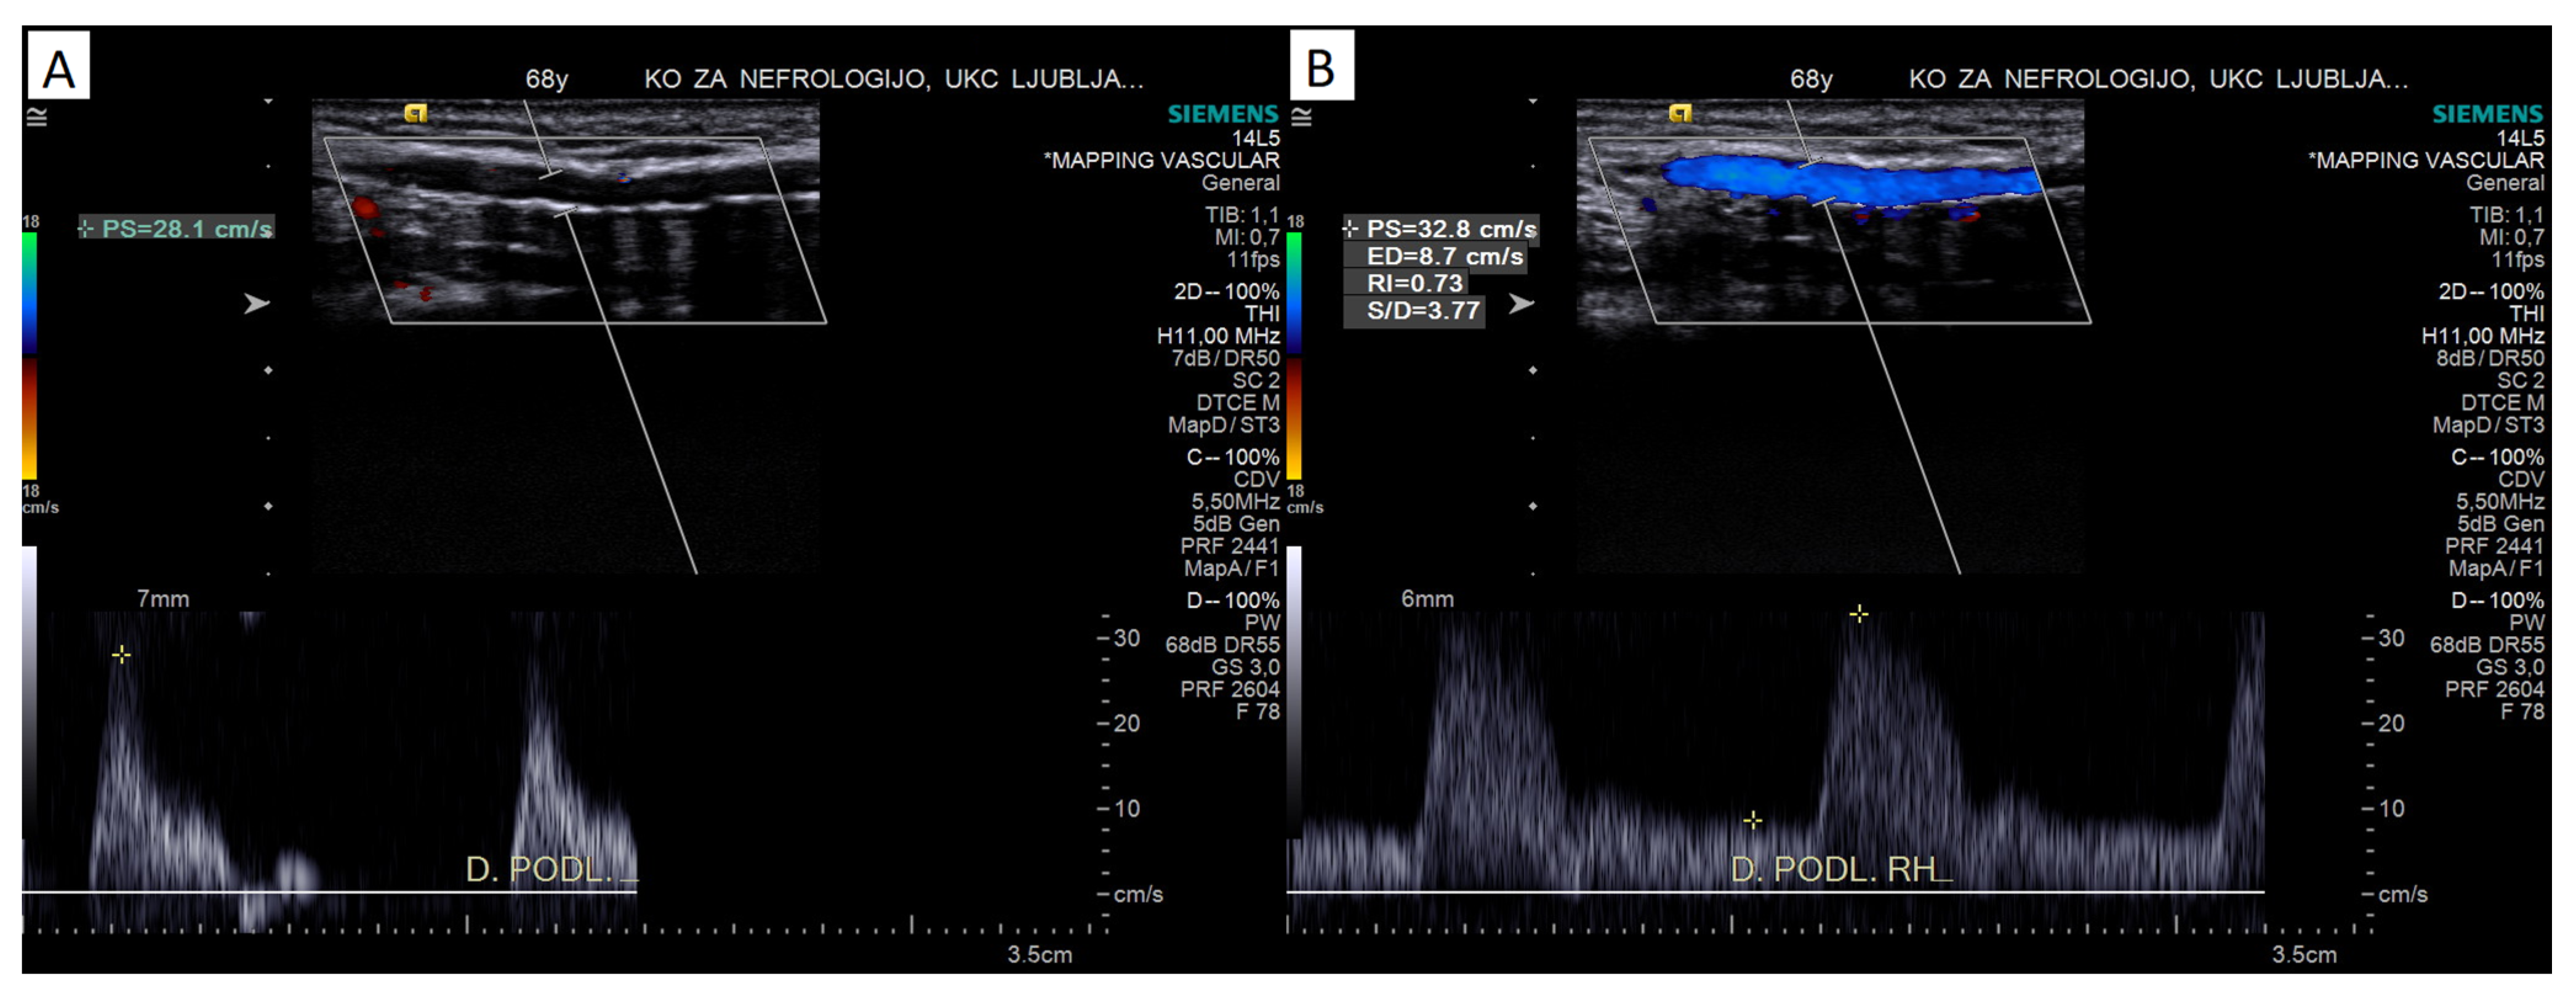

4.2.2. Pulsed-Wave Doppler Assessment

Peak Systolic Velocity

Reactive Hyperemia Test